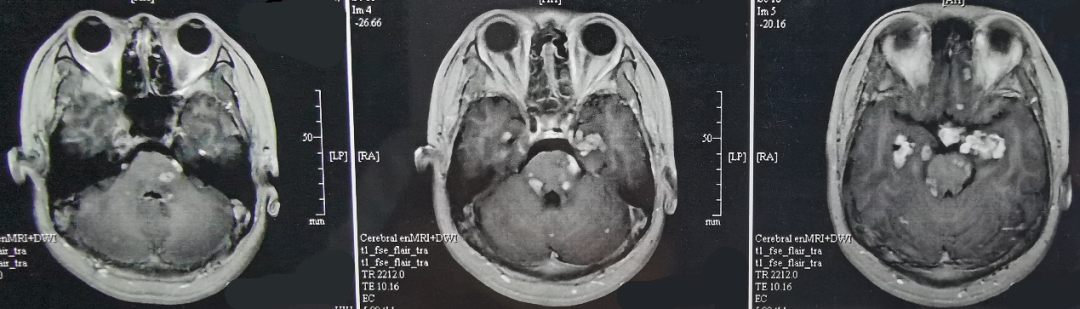

2020年5月,MRI提示病灶增大,尤其是左颞内侧病灶更为明显(图3)。进一步PET-CT检查,提示颅内多发局灶FDG代谢异常升高(片子遗失)。

图3、第2次手术前头颅MR增强影像。